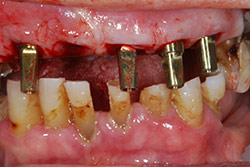

Riabilitazione implanto - protesica superiore ed inferiore in un paziente di 84 anni

Con protesi fissa superiore e protesi fissa inferiore

I denti irrecuperabili dell'arcata superiore ed inferiore del paziente di anni 65 sono stati sostituiti da 10 impianti, cioè protesi radicolari endo-ossee che sostengono le protesi fisse superiore ed inferiore.